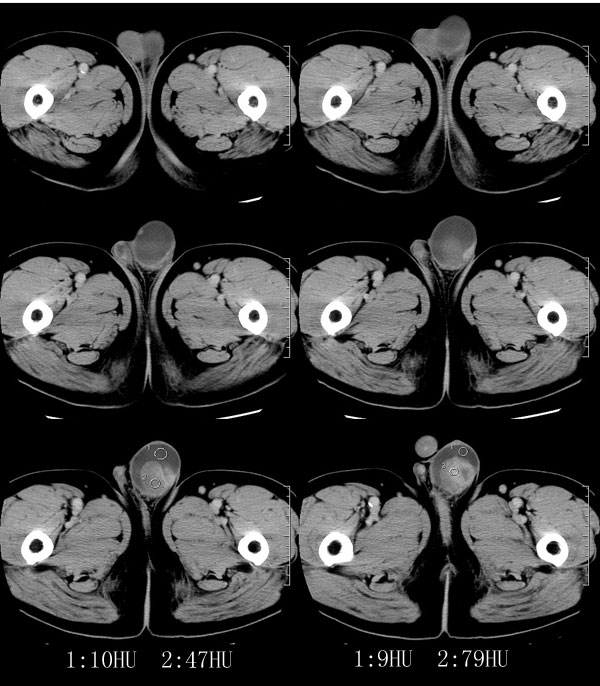

| 男性,69岁。自2个月前开始无意中发现左侧阴囊内一鸡蛋大小肿物,当时无伴疼痛等不适,未予重视。肿物逐渐增大,近段时间常伴左会阴部、腹股沟区牵扯不适,并于2周前在我院门诊行彩超检查提示“左侧附睾肿瘤可能,左侧睾丸鞘膜积液”。 专科检查:左侧阴囊肿大,其内可触及一鹅蛋大小肿物,表面光滑。肿物前部呈囊性感,后部质硬,按压无疼痛,无缩小,活动度良好。左侧睾丸未触及,透光试验(±)。                 王仕学发言:左侧睾丸见一密度不均肿块,边缘清楚,周围见水样密度影;考虑睾丸生殖细胞性肿瘤可能性大. 睾丸肿瘤占生殖系统肿瘤的3%-5%,占男性恶性肿瘤的0.5%-1.0%,其中生殖细胞性肿瘤占95%.睾丸肿瘤包括生殖细胞和非生殖细胞肿瘤两大类,前者占95%以上,后者不到5%.非生殖细胞肿瘤虽少见,但种类繁杂,主要有支持细胞、间质细胞和支持细胞-间质细胞瘤等功能性肿瘤,和间皮瘤、腺癌、横纹肌肉瘤、粘液性囊腺瘤、纤维上皮瘤、黑素神经外胚瘤、淋巴瘤等附属组织肿瘤。不同的病理类型的睾丸肿瘤发病率高峰不同,睾丸癌多发于35岁以前,精原细胞瘤发病高峰为30-35岁。精原细胞瘤约占睾丸肿瘤的60%,发病高峰在30-35岁。85%的患者睾丸有明显肿大,肿瘤局部侵犯力较低,肿瘤一般有明显界限。 手术:行“左侧附睾、睾丸、精索切除术”。 病理诊断:(左睾丸、附睾)肿物,为低分化腺癌。另送检(左精索远端)肿物,镜下亦为低分化腺癌。 免疫组化:ck(l)(++++)、cea(+++)、ca19-9(-)、psa(-)、plap(-)、p53(-)、vimentin(-)。 原贴地址:http://www.radinet.com.cn/forum_view.asp?forum_id=4&view_id=30707 |